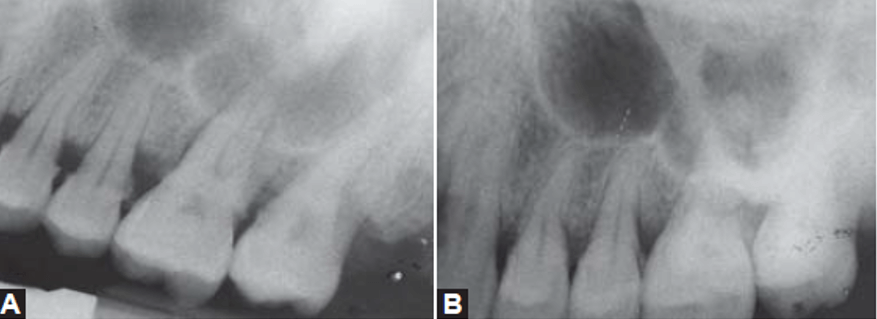

Las radiografías juegan un papel importante en el diagnóstico de la enfermedad periodontal, sin embargo, estas pueden tener limitaciones como en el caso de una la periodontal severa donde no se llegan a observar signos radiográficos de esta. Las proyecciones radiográficas útiles para el diagnóstico en periodoncia incluyen la radiografía periapical, la radiografía de aleta de mordida y la radiografía panorámica; siendo la radiografía periapical con técnica paralela la de principal elección para la evaluación de enfermedad periodontal, ya que la técnica de la bisectriz puede mostrar mayor o menor reabsorción ósea de la cual realmente presenta el paciente. Las radiografías de aleta de mordida tomadas verticalmente pueden utilizarse para evaluar la altura de la cresta ósea, cuando la perdida de esta ha sido considerable, siendo de mayor utilidad para la evaluación postratamiento o como una radiografía de seguimiento. Las radiografías de aleta de mordida tomadas horizontalmente no son útiles para evaluar la reabsorción óseas severas, pero son útiles para la evaluación de caries interproximal o recidivante. Entre las radiografías útiles para la evaluación periodontal, la radiografía panorámica es la de menor precisión ya que solo es útil para una evaluación general del soporte óseo alveolar. No obstante, esta radiografía tiene un campo amplio de evaluación para poder evaluar casos como terceros molares impactados bilaterales comprometiendo el hueso alveolar de una segunda molar o múltiples coronas protésicas desadaptadas y sobreobturaciones que condicionen la pérdida ósea alveolar, aunque en la mayoría de estos casos siempre será necesaria la ampliación del estudio con radiografías periapicales para una mejor evaluación de la zona.

Las radiografías pueden llegar a detectar signos tempranos de la enfermedad periodontal, como la irregularidad de la cresta o la perdida ósea a nivel interseptal debido al aumento del ensanchamiento de los canales nutricios. Así mismo, la cresta ósea se presenta irregular y con interrupción de la integridad de la lámina dura por mesial y distal del hueso alveolar interdental. Otro signo temprano es la triangulación, que se define como el ensanchamiento del espacio periodontal, con sus lados formados por la lámina y la superficie radicular con su base hacia coronal.